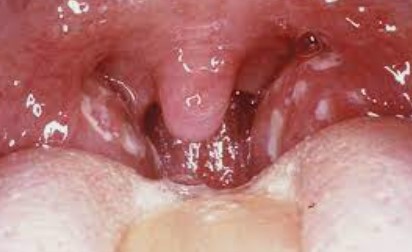

편도결석(편도결석) 이들은 편도선과 또는 편도의 틈새에서 형성되는 석회화된 물질의 덩어리입니다. 그들은 대부분 칼

슘으로 구성되어 있지만 마그네슘, 인과 같은 다른 성분을 포함할 수 있으며 편도선에 작은 덩어리처럼 느껴질 수 있습

니다. 드물게 유해하지만 성가시고 제거하기 어려울 수 있으며 종종 구취를 유발할 수 있습니다.

편도 결석 제거법은 아래 링크를 확인하시면 큰 도움이 될 거예요.

양치질을 열심히 했는데도 입에서 구취가 나시나요? 간혹 재채기를 하면 노란 콩알 같은 노란 알갱이가 입에서 튀어나오나요? 입을 벌려 목을 들여다보면 목안 벽(편도선)에 노란 결석이 박혀있